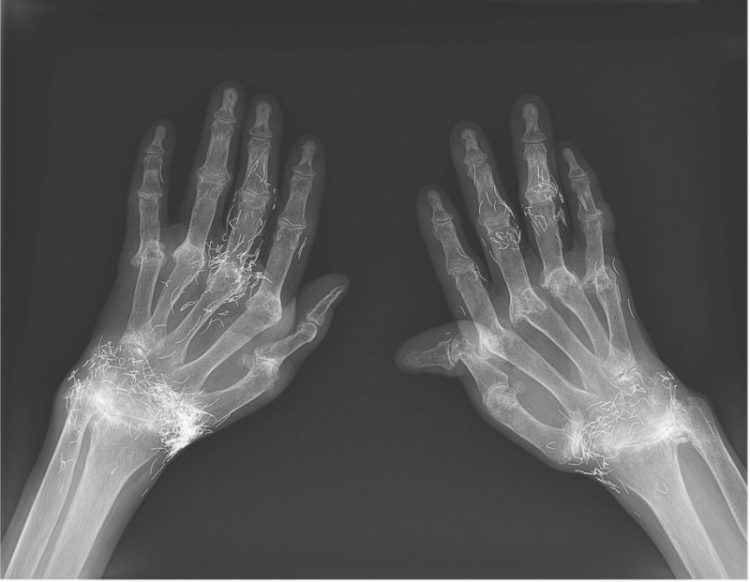

Photo: The New England Journal of Medicine

An X-ray exam revealed a thickening and hardening of the inner part of the tibia, bony growths in the knee, all common symptoms of osteoarthritis – but also hundreds of tiny gold threads embedded in the tissue around the knee. Doctors warn that gold thread acupuncture has no scientifically-proven benefit for the patient, but comes with many known risks. The tiny threads can cause cysts, migrate into the body, and damage surrounding tissue, but they can also make potentially life-saving MRI scans impossible because of the risk of metal displacement and blood vessel damage.